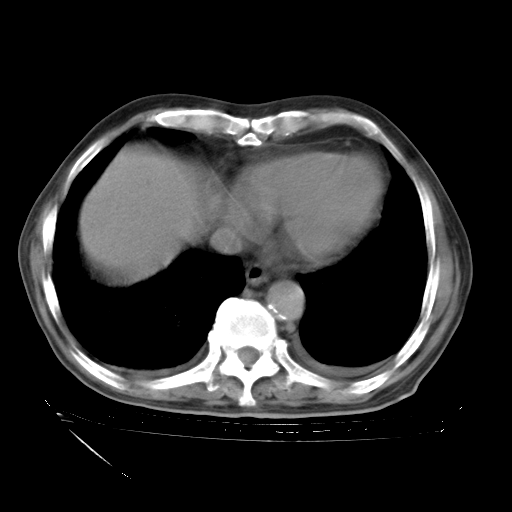

甲强龙80mg/日+抗结核治疗(异烟肼+利福霉素+乙胺丁醇)10天。复查肺部CT。

治疗10天肺部CT

补充下:5月9日胸部CT:似乎已见双下肺胸腔积液了,鉴于目前有下肢水肿,肝功示:白蛋白低,应注意多浆膜腔积液(漏出液可能大?),需注意!